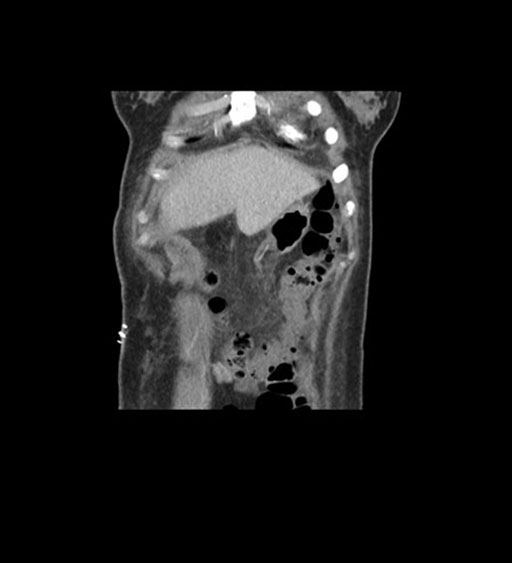

Imaging Analysis

Look through the patient's CT scan to identify any areas of concern for the necessary procedure.

Coronal Arterial

Coronal Venous